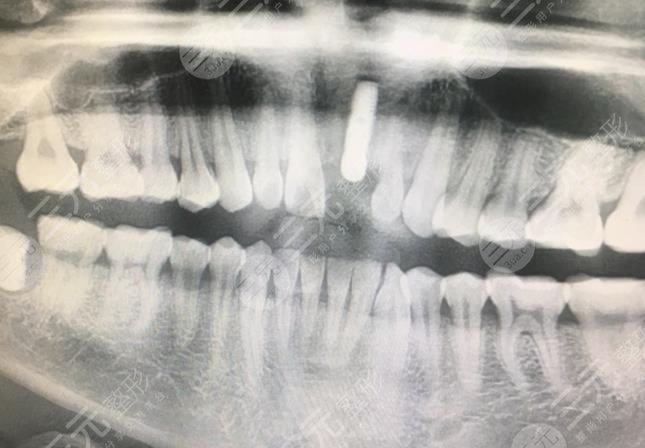

我是一个程序员,每天都会熬夜工作,身体的机能大量的下降,其实牙齿也并不是特别的好看,以前长过多生牙,但是因为专业医生的指导下已经将牙齿拔除了,但现在的门牙也不是特别的美观,较为的丑陋,还有一点脱落的现象,吃东西也较为的不方便。为了让自己能够吃想吃的东西,也为了让自己的口腔状态变得更加的精美一点点,去到了专业的整形医院进行了诊断,然后牙科的专业医生说可以做种植牙治疗,来使整个口腔变得更加的美观。

经过一系列的医学检测和诊断之后,较终确定了手术的方案就是种植牙治疗,做完手术之后,迫不及待的去镜子面前看了看自己的口腔状态,也用手机的相机照了照自己的牙齿,发现种植牙和自己原本的牙齿形态较为的合适,看不出有任何的区别,根本就没有突兀的感觉,果较为的自然和和谐。